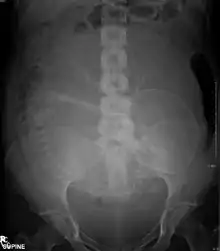

Abdominal radiograph of a pregnant woman

The risk of radiation is greater to a fetus, so in pregnant patients, the benefits of the investigation (X-ray) should be balanced with the potential hazards to the fetus.[119][120] If there is 1 scan in 9 months, it can be harmful to the fetus.[121] Therefore, women who are pregnant get ultrasounds as their diagnostic imaging because this does not use radiation.[121] If there is too much radiation exposure there could be harmful effects on the fetus or the reproductive organs of the mother.[121] In the US, there are an estimated 62 million CT scans performed annually, including more than 4 million on children.[109] Avoiding unnecessary X-rays (especially CT scans) reduces radiation dose and any associated cancer risk.[122]